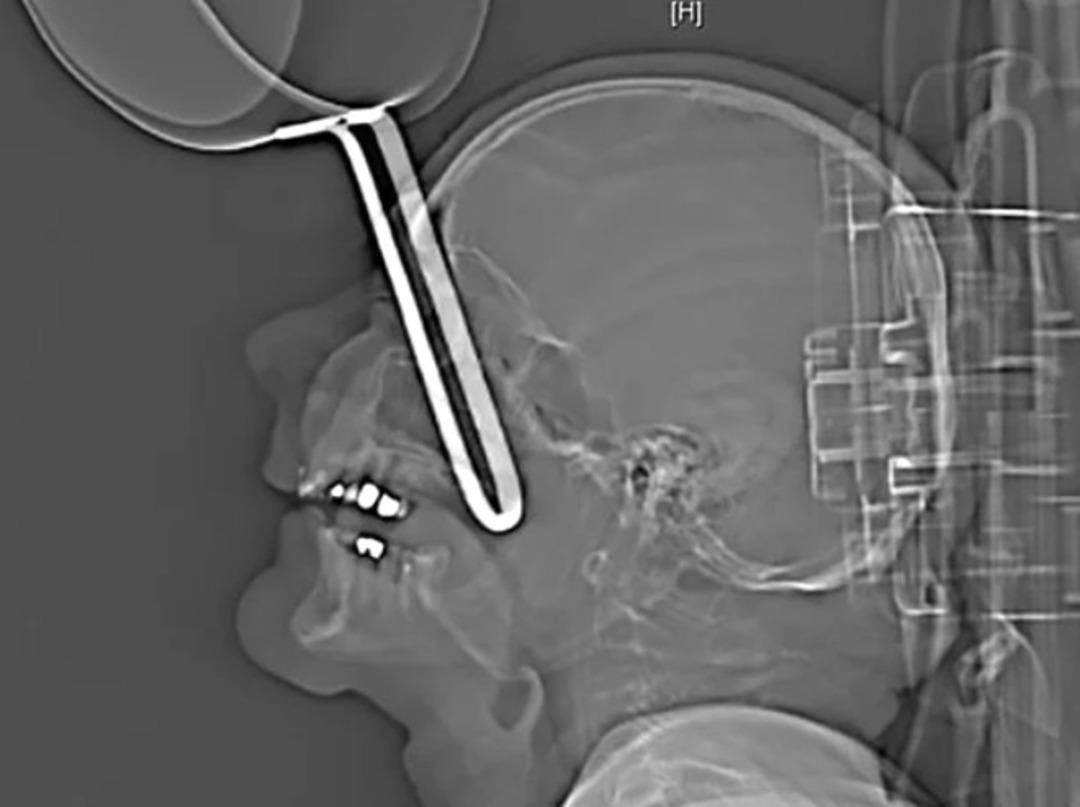

İsmi açıklanmayan 64 yaşındaki adamın hastanede çekilen röntgen filmi olayı aslında gayet açık gösteriyor. Evinin mutfağına sarhoş geldikten sonra, düşen ve tencere sapıyla birlikte yüzüne saplanan adam mucize bir şekilde acil servisi kendisi aradı.

Dr. Carla Sander'in başında bulunduğu tıbbi ekip, adamın kafatasının röntgenini çekti ve acil müdahalede bulundu. Doktor Sander bulguları şöyle açıklıyor; "Tencere sapı kafatasının içine 10 cm kadar saplanmış, üst kısımdan gelerek orbitanın önündeki açıklığı delerek içeri girmişti.

Doktorlar adamın oldukça şanslı olduğunu düşünüyor. Çünkü tencere göz boşluğunun altından girip ne göze ne de beyine zarar vermedi. Daha sonra cerrahi operasyonlarla yaşlı adam eski sağlığına kavuştu